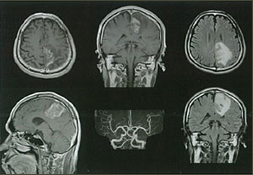

• 目的に応じて優れた画像コントラストが得られます。たとえば、脳や脊髄などの中枢神経系などを鮮明に診断できます。また、脳幹部もCTより非常によく描出され、血管描出に優れ、頭部血管、頸部血管までも立体的に描出し、従来のMRIよりさらに画像が良くなっています。縦・横・斜めと任意に様々な断面での撮影による3次元画像での診断ができ、脳の下部や脊髄・関節の中などを見ることができます。脊椎、頚椎の病気の中で代表的な腰椎椎間板ヘルニアや脊柱管狭窄症等の診断には、1.5テスラMRI撮影は欠かせません。